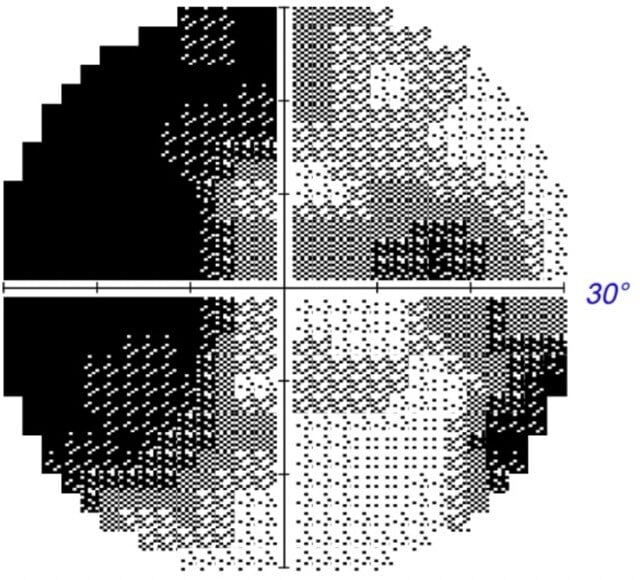

30 Grad visual field test

First Therapy: July 2022 (Baseline Visual Field)

Right eye

Left eye

At baseline, Khanh’s visual field showed severe defects in both eyes:

- Right Eye (RE): A VFI of 14% and an MD of -27.05 dB indicated near-complete loss of function, with only fragmented sensitivity in the central and peripheral fields.

- Left Eye (LE): A VFI of 22% and an MD of -25.59 dB demonstrated severe damage, though slightly better than the RE. Blind spots and scotomas were prominent across both eyes.